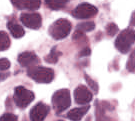

As an essential part of digital pathology, histopathology image analysis is playing increasingly important role in cancer diagnosis, which can provide direct and reliable evidence to diagnose the grade and type of cancer. This paper deals with nuclei segmentation, an important step in histopathological image analysis. The purpose of nuclei semgentation is not only counting the number of nuclei but also obtaining the detailed information of each nucleus. So unlike nuclei detection, here the outputs are the contour of each nucleus instead of only the position of their central points. Hence we can exactly extract each nucleus from the image and make it available for further analysis. For example, the features of the individual nucleus and the distribution of nuclei clusters can be used to grade and classify status of breast cancers [3, 4]. Because of appearance variation such as color, shape, and texture, nuclei segmentation from histopathological images could be very challenging, as illustrated in Fig.1, in which it is very challenging even for human to recognize and segment all nuclei within the images. Fig.1(a) and Fig.1(b) illustrate two histopathological images from different organs. Fig.1(c) and Fig.1(d) are two histopathological images from same organ but have different cancer grade.

H&E stain is the most widely used stain protocol in medical diagnosis. Typically, the nuclei of cells are stained to blue by Haematoxylin while cytoplasm is colored to pink by Eosin. But in practice, the color of H&E stained images could vary a lot due to variation in the H&E reagents, staining process, scanner and the specialist who performs the staining, as shown in Fig.1. A few H&E stain normalization methods[23, 24, 25] have been proposed to eliminate the negative interference caused by color variation. We tried two of them[23, 25] to normalize the raw H&E stained images. For our segmentation algorithm, we did not find any considerable difference between these two normalization methods. Particularly, the result shown in experiment section III is generated based on the images normalized by the method in [23]. Given a target image, this method is able to convert one image’s color into the target image’s color space based on sparse non-negative matrix factorization(NMF). We choose one best stained H&E image as the target and convert other images into its color space. According to the recommendation in [23], the hyper-parameter should be set between 0.01 and 0.1. In our experiment, is set to 0.1.